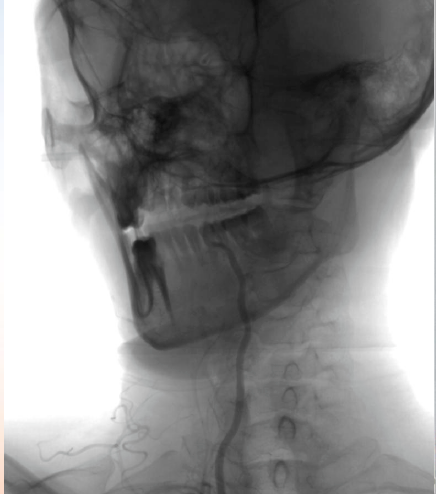

初始造影RICA起始位

病历夹什么径技·第152期|串联营病历夹:川陕大营_https://www.jmylbn.com_新闻资讯_第81张

初始造影后循环+LICA正位

病历夹什么径技·第152期|串联营病历夹:川陕大营_https://www.jmylbn.com_新闻资讯_第82张

手术方案

初始治疗:rtPA静脉溶栓0.9mg/Kg

进一步治疗:溶栓后2小时候复查头颅CT检查未见出血,使用替罗非班静脉泵入治疗

入院后31小时病情加重

查体:嗜睡,构音障碍,双眼向右凝视,左侧面瘫,左侧肢体上下肢均为0级,NIHSS 15(+10)

复查头颅CT未见出血

手术过程

在Synchro微导丝与Rebar-18支架导管的辅助下顺利超选上去,借助Transend导丝使用球囊穿梭技术将Sprinter(3*15)球囊装入血管真腔中。

过程影像

病历夹什么径技·第152期|串联营病历夹:川陕大营_https://www.jmylbn.com_新闻资讯_第83张

病历夹什么径技·第152期|串联营病历夹:川陕大营_https://www.jmylbn.com_新闻资讯_第84张

<<滑动查看下一张图片>>

由于guiding通过失败所以先处理近端,将Spider FX(5)保护伞置入进行了远端保护,近端放置了WALLSTENT支架,然后收伞,顺势将guider通过,结果其无法到达远端。